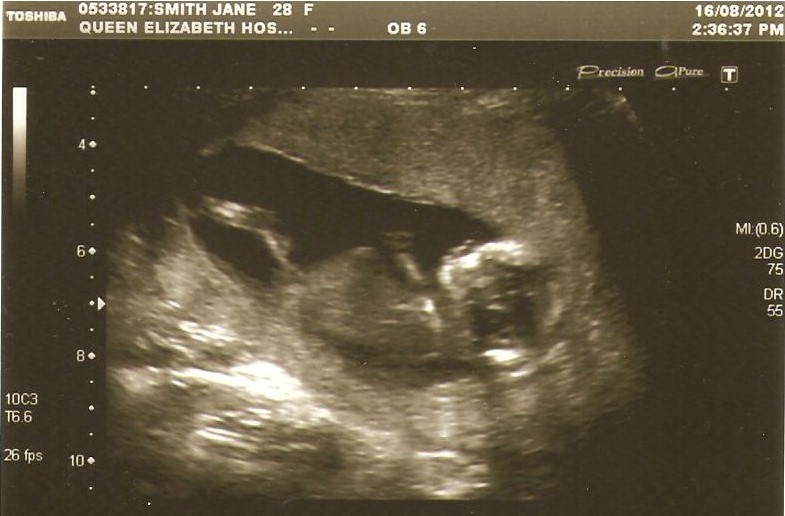

Almost impossible to tell... But I'd guess boy. (looks like a tiny penis and scrotum) :)